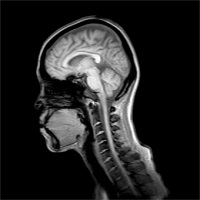

元女囚が教える覚醒剤の基礎知識――14歳からシャブ使用、大山倍達孫は脳が縮んでるかも?